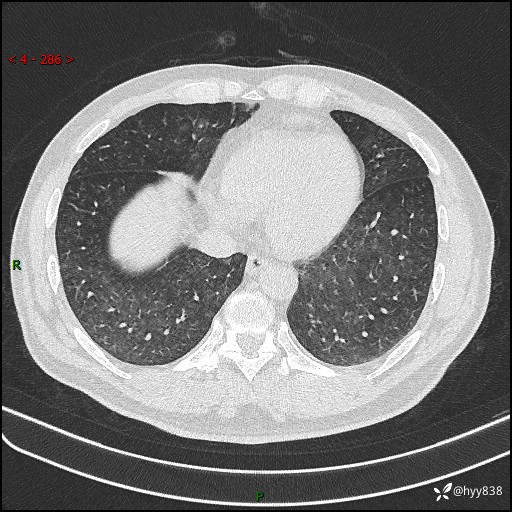

辅助检查:CT

胸部HRCT